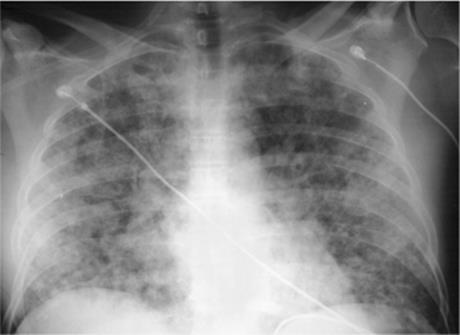

This describes replacement of the airspaces with fluid or exudate without gross destruction or displacement of lung morphology. Signs of airspace disease (Chapter 14) (Fig. 5.5) occur. At CT early airspace disease may manifest as ground glass opacity, with increased attenuation but with pulmonary vessels still visible.

Figure 5.5 Airspace disease at computed tomography. Pneumonia shows air bronchograms (arrowheads), lobar distribution (arrowsdenote major fissure), and ill-definition anteriorly.